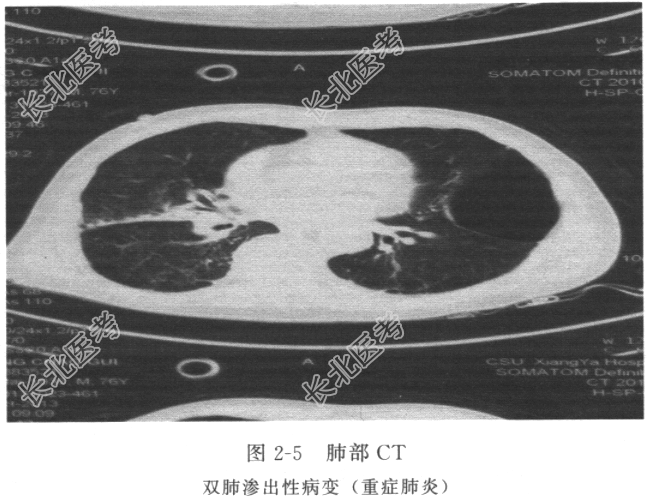

辅助检查 肺部CT(图2-5)示双肺渗出性病变;血象高。血气分析示pH 7.51,PaCO2 36mmHg,PaO2 47mmHg,BE 0.3mmol/L。

入院诊断 重症肺炎;心肺复苏术后;糖尿病。